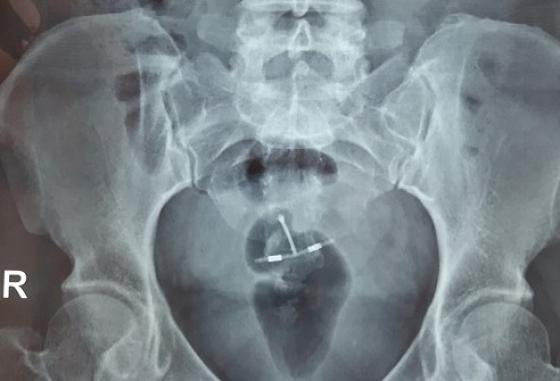

Khi chụp X-quang cách đây 4 năm, Ortiz phát hiện một đoạn dây kim loại lạ chạy từ động mạch chủ xuống đùi của mình. Các bác sĩ đã loại bỏ một phần của đoạn dây vào năm 2018 nhưng vẫn sót lại khoảng 50 cm trong cơ thể bệnh nhân.

Luật sư của nguyên đơn cho biết đoạn dây lạ kia chính là một ống thông cần thiết phải đưa vào trong quá trình phẫu thuật mạch vành. Tuy nhiên, bác sĩ Taylor đã bỏ quên đoạn dây trong khi đáng lẽ phải rút nó ra trước khi kết thúc ca mổ.